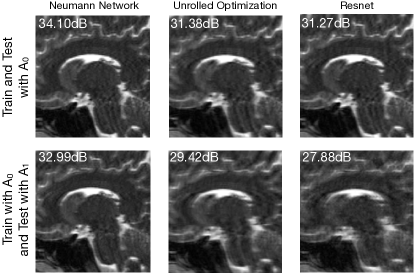

Robustness to different forward model at test time than at train.

In some settings, the forward model used during training is different from the forward model used during testing. For example, imagine learning to reconstruct MRI images for a scanner at one clinic and then attempting to use that learned algorithm to reconstruct MRI images for a (subtly different) scanner at another clinic. The different methods described in Section 4 will have different degrees of robustness to perturbations in the forward models between training and testing. This is illustrated in Figure 11 for a few representative methods.